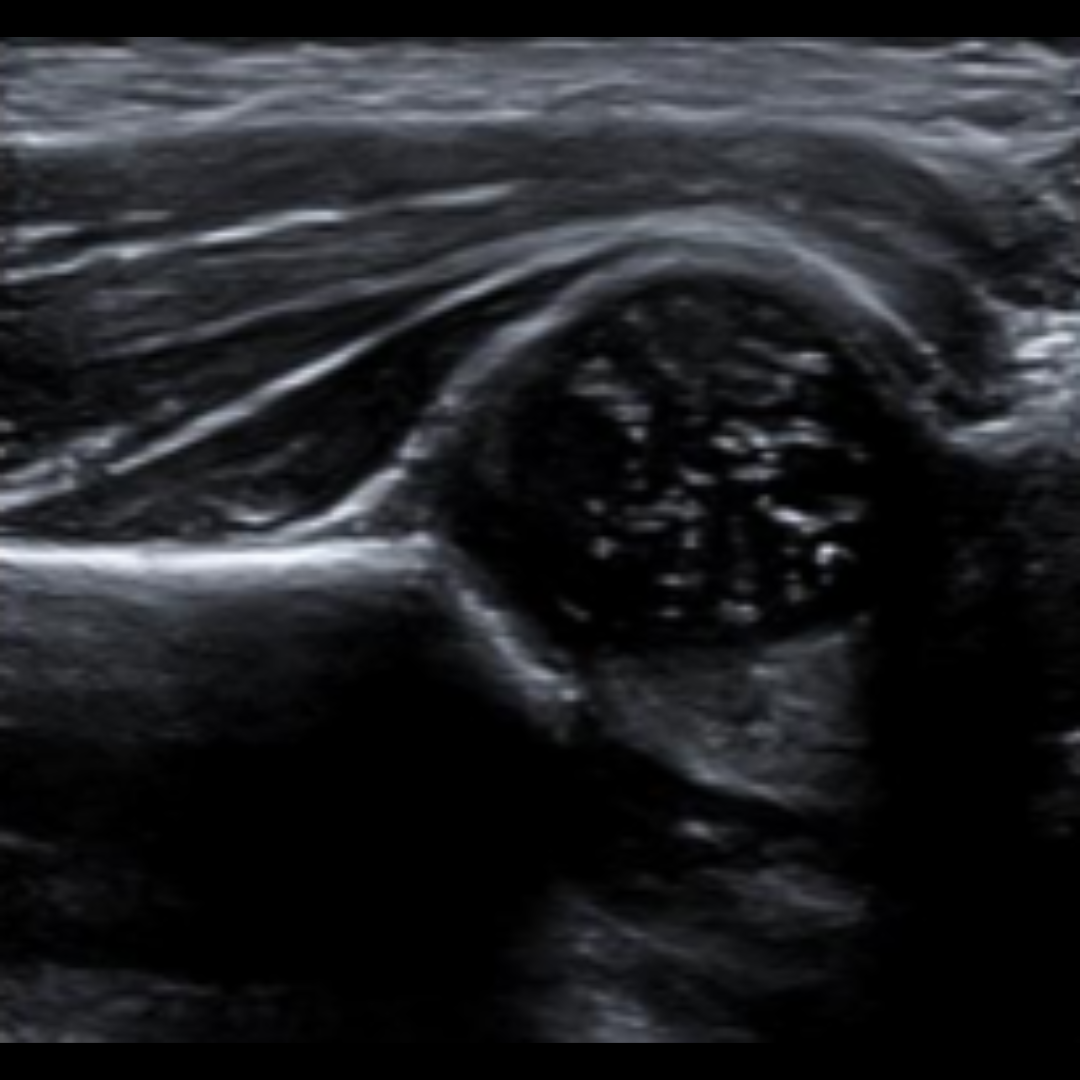

Ecografia Testicular

Estudia los testículos y el escroto en casos de dolor, inflamación o sospecha de torsión testicular o testiculo no descendido. Es rápida y segura, fundamental ante urgencias u otras molestias genitales.